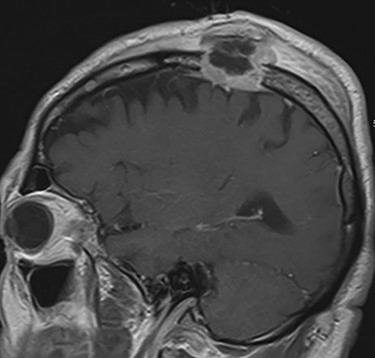

Noncontrast head computed tomography (CT) confirmed a left parietal bone lytic lesion (Fig. 1). Brain magnetic resonance imaging (MRI) confirmed an enhancing mass involving the left lateral scalp and parietal bone extending down to the dura (Fig. 2). T1-weighted image noted additional small enhancing lesions of the frontal calvarium. Initial laboratory studies noted hypercalcemia (serum calcium 10.6 mg/dl) and anemia (hemoglobin 11.5 g/dl).

MRI brain T1 postcontrast view (sagittal plane) showing an avidly enhancing mass eroding through the left parietal bone and extending deep to the dura with scalp edema and thickening, in addition to smaller enhancing lesions of the frontal calvarium.